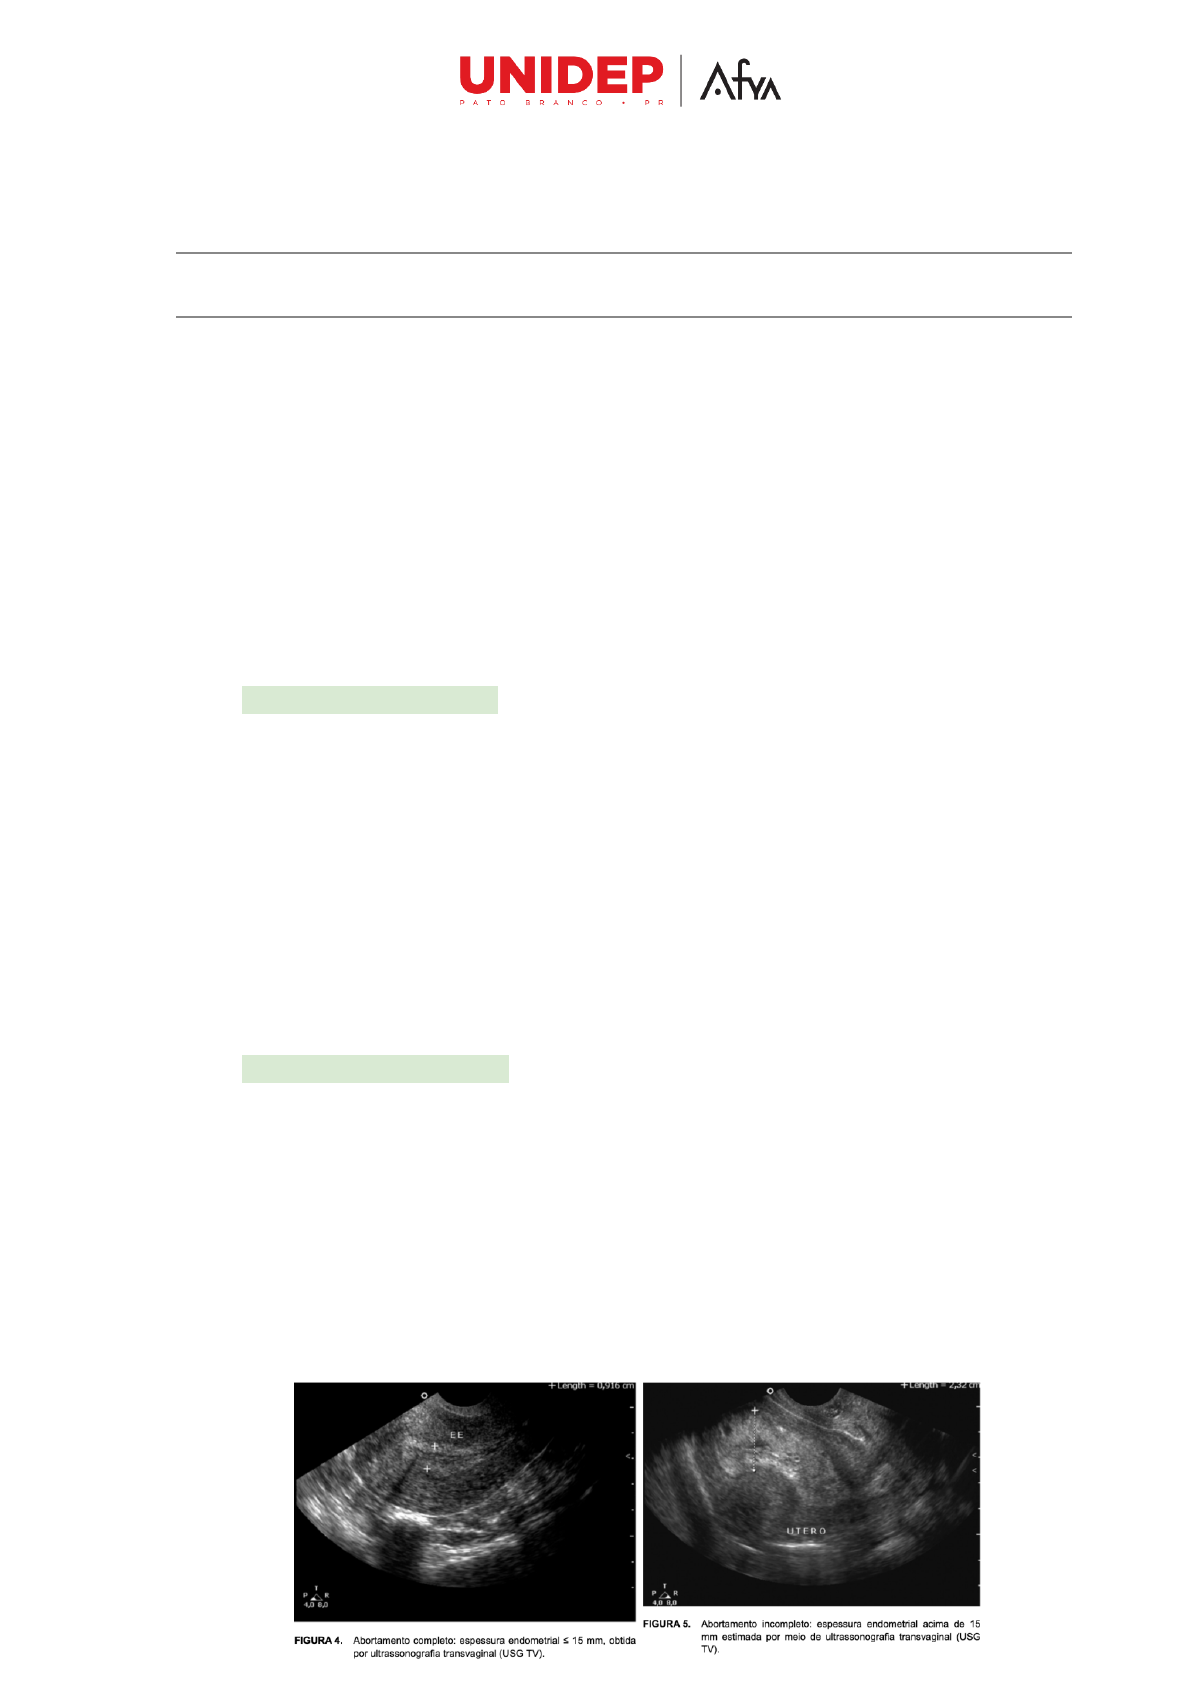

Abortamento completo: Expulsão completa do embrião ou feto. É comum

quando o aborto ocorre no 1o trimestre da gravidez, principalmente nas 10 semanas

iniciais.

● Rapidamente, o útero se contrai e o sangramento e as cólicas diminuem de

intensidade.

● O orifício interno do colo uterino tende a fechar-se em poucas horas.

● Pode não haver conteúdo uterino no USG, mas, algumas vezes, observa-se

pequena quantidade de conteúdo heterogêneo e líquido.

● A medida da espessura endometrial de até 15 mm ao corte longitudinal

mediano do útero à USG transvaginal tem sido considerada iniciativa de

aborto completo.

Abortamento incompleto: ocorre eliminação parcial do feto ou embrião. É mais

frequente após 10 semanas de gravidez.

● O sangramento vaginal persiste e, por vezes, torna-se intermitente.

● O volume uterino é menor que o esperado para a idade gestacional.

● No exame de toque: o orifício interno do colo uterino geralmente encontra-se

pérvio, podendo, entretanto, algumas vezes apresentar-se fechado.

● USG: mostra a presença de conteúdo intrauterino de aspecto amorfo (forma

indefinida) e heterogênea, com presença ou não de líquido.

● A espessura endometrial acima de 15 mm tem sido considerada indicativa de

aborto incompleto.